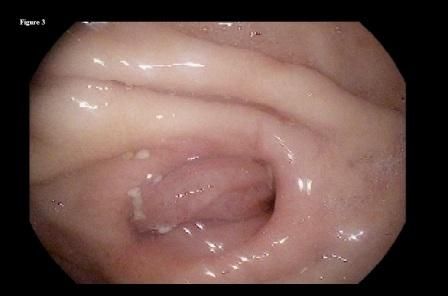

Figure 3.

She followed this regimen for the following 3 months with significant improvement in her symptoms. A repeated upper endoscopy performed at 3 months after presentation showed complete dissolution of the phytobezoar, with a clear view of the distal end of the gastric remnant (Figure 3) and the jejunal side of the anastomosis (Figure 4).